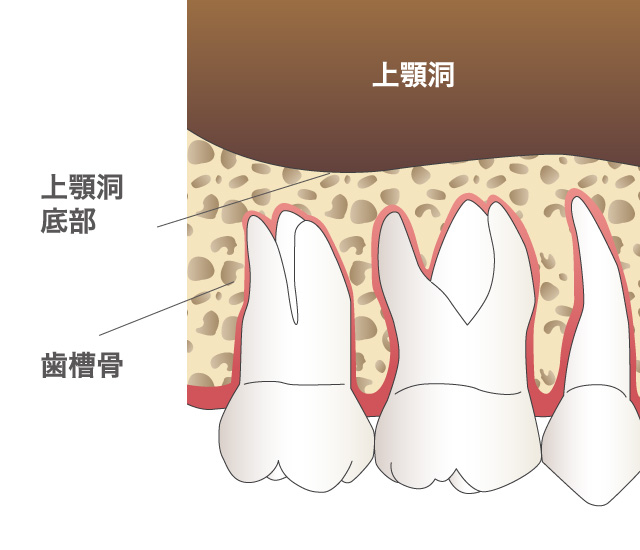

インプラント治療とは術前診査・診断を十分に行った上で、歯が抜けてしまった部分にインプラント(人工歯根)を埋め込み、その上から自然な見た目の人工歯を装着させるという治療法で、骨にしっかりとインプラント(人工歯)を定着させるため、自分の歯のようにしっかり、思い切り噛めるようになります。